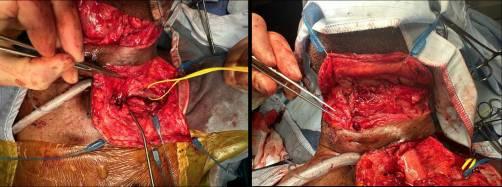

钡剂吞咽荧光镜检查报告食管道不规则,吞咽时吸入造影剂,并发现食管肿块(图1)。颈部、胸部、腹部和骨盆的计算机断层扫描(CT)显示食管壁增厚,表明食管和近端气管之间存在瘘管,以及感染引起的双侧磨砂玻璃阴影(图2)。值得注意的是,初次报告中没有提到异物。食管胃十二指肠镜(OGD)对距离切牙19厘米处的肿块进行了评论,显示在此水平上有一个“大的、有柄的息肉”样病变,很难进行组织活检。

图1 术前吞钡透视。气管和食管显示对比(红色箭头),表明存在瘘管